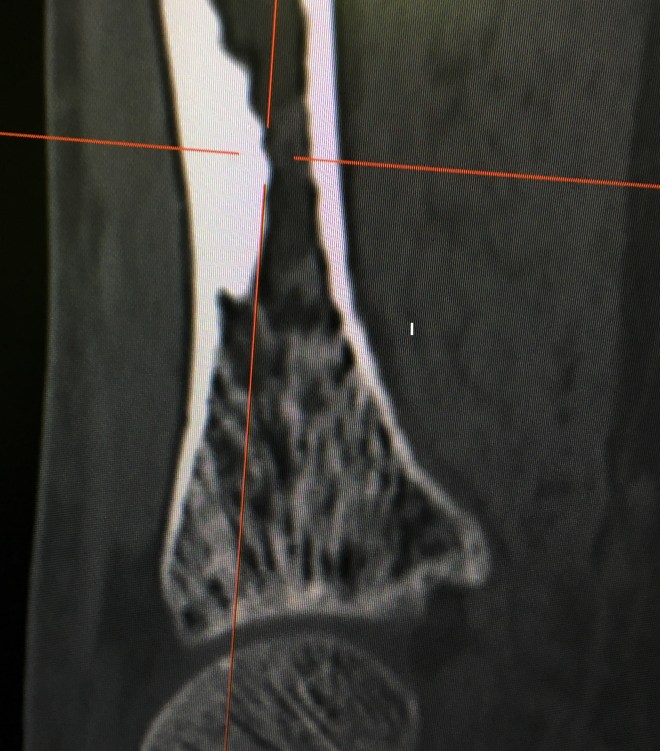

Previous ImageNext Image Intracortical Tumor CT scan Sagittal CT view C. bakshiortho.com Like Loading...